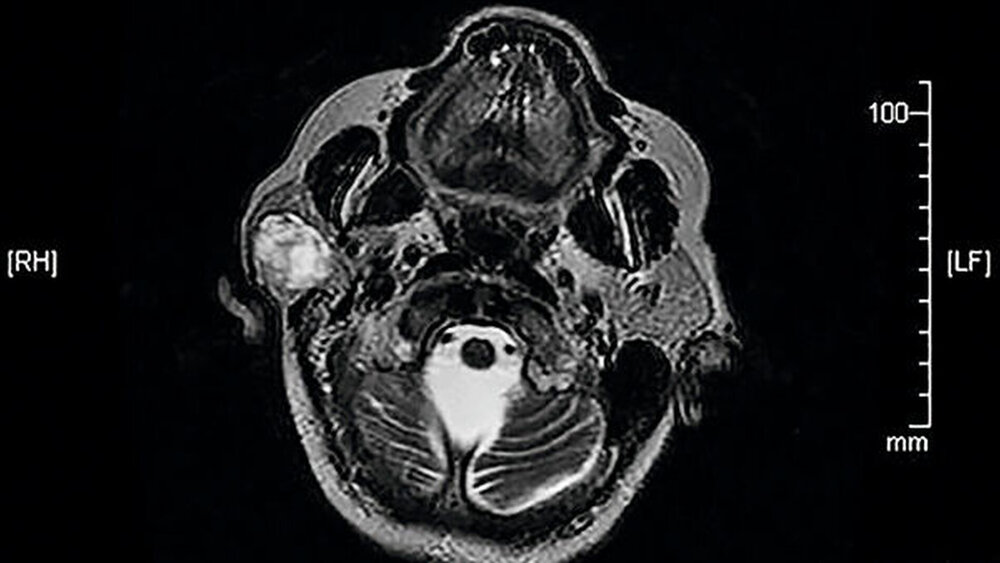

Eine 81-jährige Patientin wurde bei einer anamnestisch vor drei Jahren erstmals aufgefallenen und seither größenprogredienten Schwellung präaurikulär rechts (Abbildungen 1 bis 3) mit der Bitte um Weiterbehandlung an die Klinik für Mund-, Kiefer- und Gesichtschirurgie der LMU München überwiesen. Die alio loco durchgeführte bildgebende Diagnostik mittels MRT hatte einen abgegrenzten Prozess in der rechten Glandula parotidea gezeigt (Abbildungen 4 und 5). In der Zusammenschau der klinischen und der radiologischen Befunde wurde die Verdachtsdiagnose eines pleomorphen Adenoms im Bereich der Glandula parotis rechts gestellt.